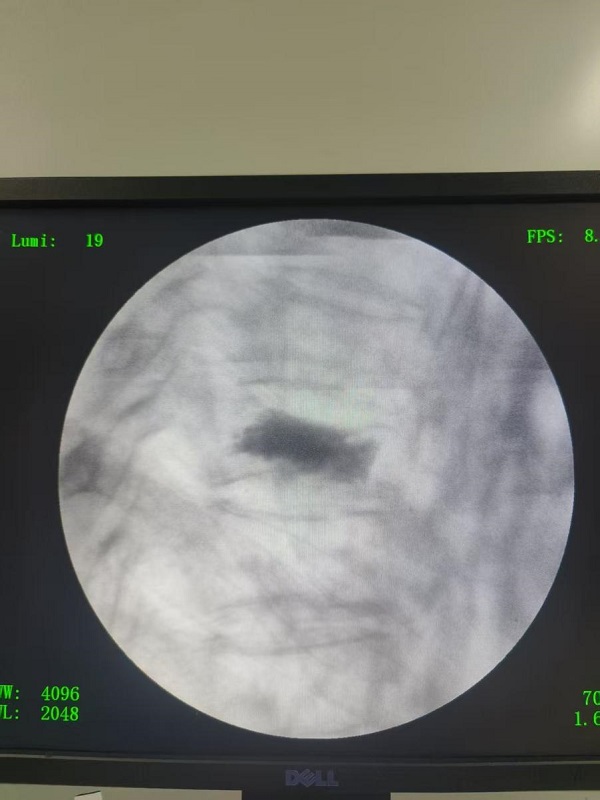

手术当天,麻醉科团队全程护航,尤其彭爷爷有肺心病,重度支气管扩张,经常气喘、咳嗽,在俯卧位下行高位胸椎手术,既要患者采用先进的局部麻醉联合镇静技术,确保术中患者无痛感,又最大限度减少对心肺功能的影响。在清醒状态下俯卧位轻松配合手术,全程无不适,还与医护人员亲切交谈。仅用30分钟,手术顺利完成。术后X光显示骨水泥填充完美,骨折椎体即刻恢复稳定。

“真神奇!刚做完手术背就不疼了,胸部也不痛了!”术后第二天,彭爷爷已戴护具独立下床行走,笑容满面地竖起大拇指:“现在腰板直了,走路也有劲了,终于能回家抱孙子了!”出院前复查显示,彭爷爷的胸椎高度完全恢复,疼痛缓解明显,生活质量显著提升。